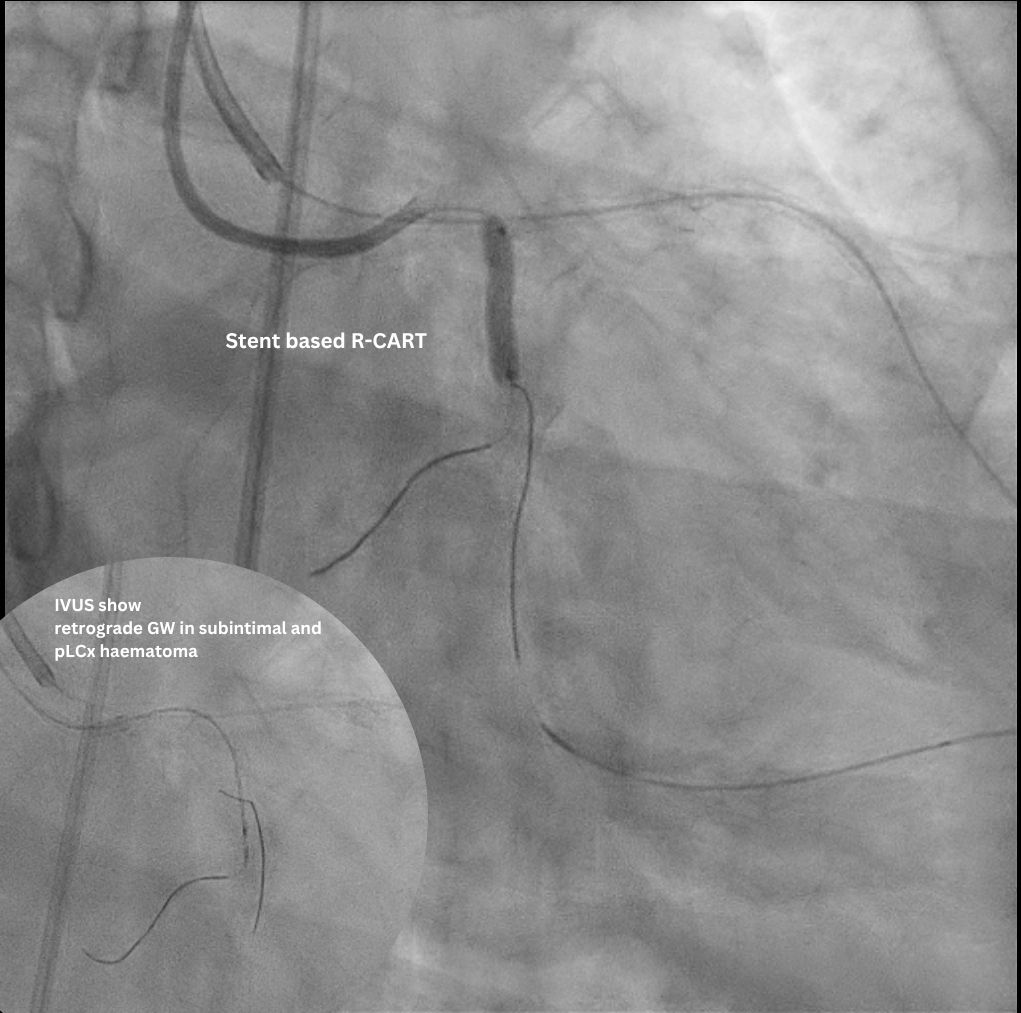

Access was achieved via RRA and US-guided RFA puncture. A 7F SBP 3.5 guide was engaged to LM, and a 6F IL 3.5 guide was in oRCA, confirming no contralateral supply to LCx CTO. After a failed antegrade IVUS guided puncture by GW Gaia Next 2, the strategy shifted retrograde. GW Sion supported by microcatheter Caravel successfully navigated D1 across LAD stent struts, visualizing the ipsilateral epicardial collateral to OM2. The wire was exchanged to SUOH 03 and then advanced to OM2. After initial retrograde wiring failures by a UB3, a Gladius MG successfully crossed the CTO body to pLCx. IVUS to pLCx confirmed retrograde wire in subintimal plane. Multiple attempts R-CART failed in p-mLCx despite wire escalation to GW Gaia Next 3. Repeat IVUS showed enlarging pLCx hematoma, necessitating deployment of a DES (ULTIMASTER NAGOMI 3.0 mm/18 mm) to seal the entry point. Successful stent based R-CART was then achieved with Gaia Next 3, confirmed by IVUS. The IL 3.5 guide was moved to LM as an antegrade Ping-Pong guide for RG3 externalization after successfully advancing retrograde wire and microcatheter to the IL guide. The m-dLCx was prepared by SC balloons and a DES (ULTIMASTER NAGOMI 2.5 mm/50 mm) was deployed to the p-dLCx-OM2, overlapping the proximal DES. A D1 perforation was noted and then successfully treated with fat embolism via the retrograde microcatheter. Final angiogram and IVUS confirmed optimal results.

This intervention successfully revascularized a challenging LCx CTO despite antegrade failure and absent contralateral collaterals. Success hinged on strategic retrograde access via an uncommon ipsilateral epicardial collateral from the LAD, and overcoming pLCx hematoma via a specialized, IVUS-guided, stent-based R-CART technique using localized stent deployment. The Ping-Pong guide setup streamlined the complex wire externalization process. This case demonstrates that combining advanced hybrid techniques and modifying the R-CART strategy is essential for optimal outcomes in high-complexity CTO PCI.